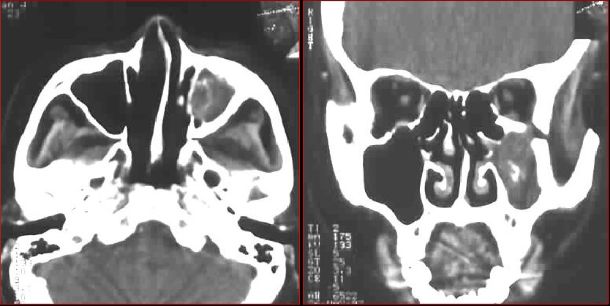

筛窦异物伴急性感染